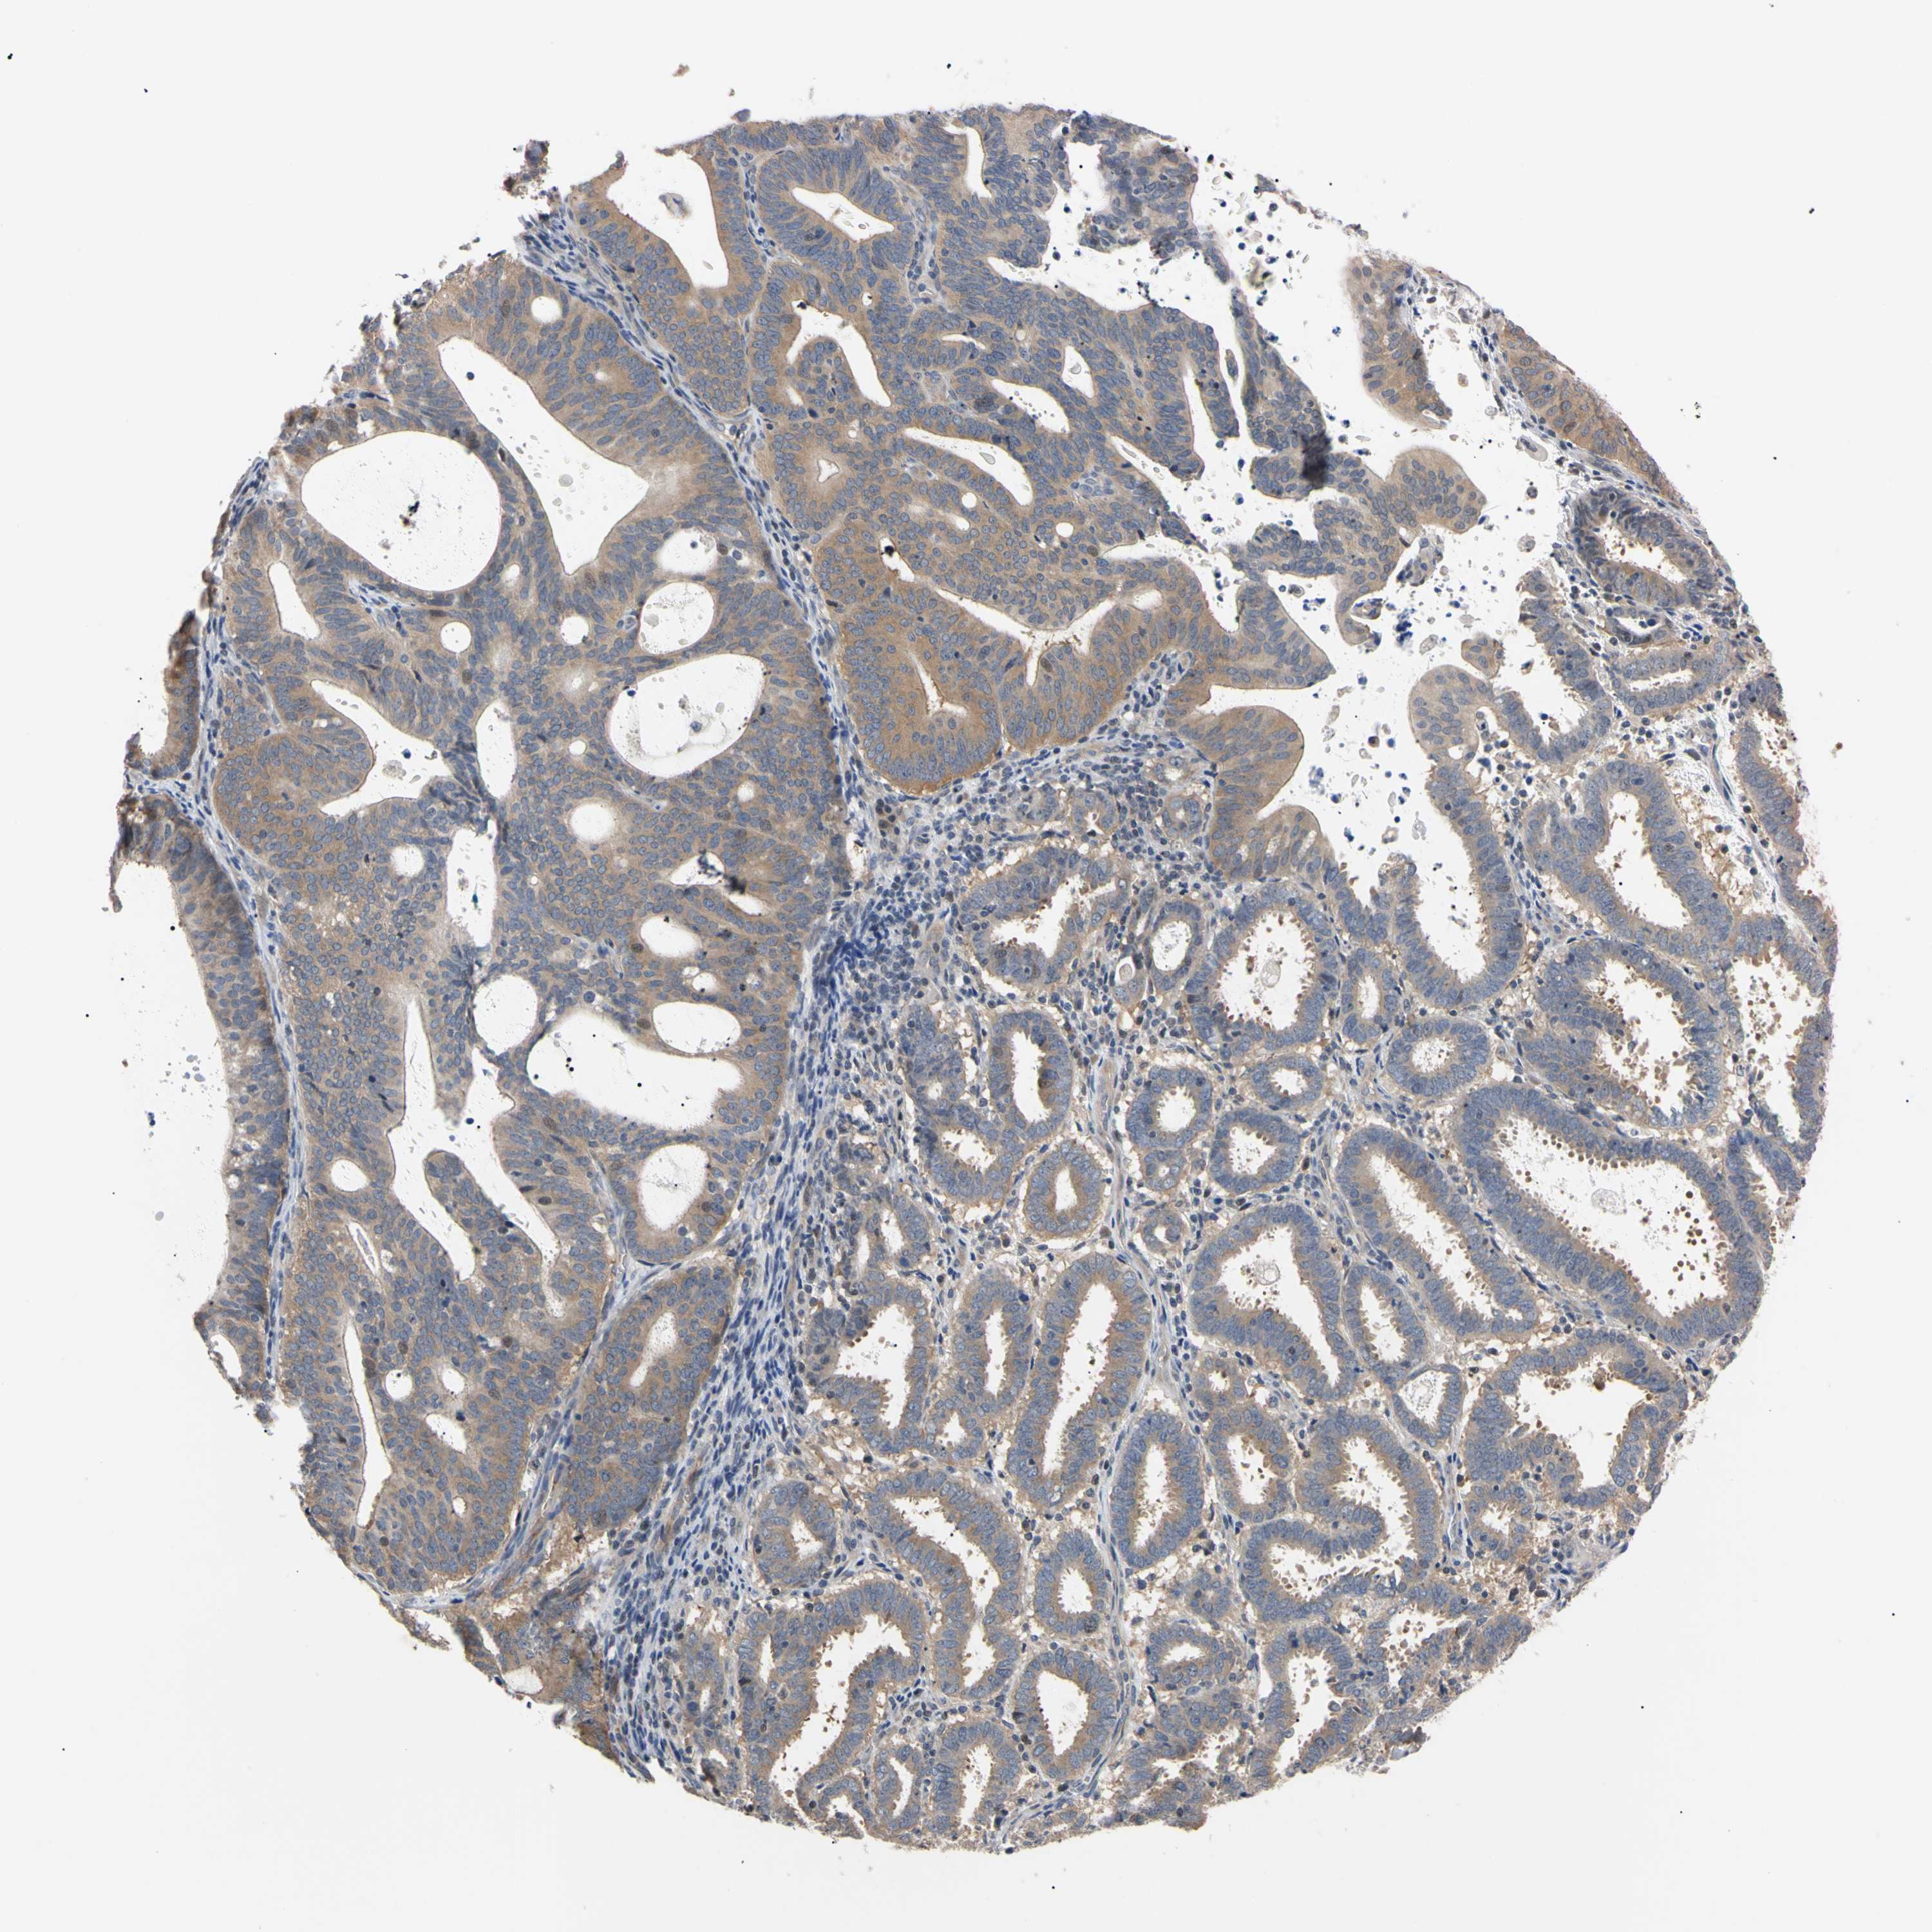

ENDOMETRIAL CANCER - Protein expressioni

A mouse-over function shows sample information and annotation data. Click on an image to view it in a full screen mode. Samples can be filtered based on level of antibody staining by selecting one or several of the following categories: high, medium, low and not detected. The assay and annotation is described here.

Note that samples used for immunohistochemistry by the Human Protein Atlas do not correspond to samples in the TCGA dataset.

Antibody stainingi

Antibody staining in the annotated cell types in the current human tissue is reported as not detected, low, medium, or high, based on conventional immunohistochemistry profiling in selected tissues. This score is based on the combination of the staining intensity and fraction of stained cells.

Each image is clickable and will lead to virtual microscopy that enables deeper exploration of all samples and also displays staining intensity scores, fraction scores and subcellular localization as well as patient and tissue information for each sample.

Antibody HPA003979

Antibody HPA004130

Staining

High

Medium

Low

Not detected

Intensity

Strong

Moderate

Weak

Negative

Quantity

>75%

75%-25%

<25%

None

Location

Nuclear

Cytoplasmic/membranous

Cytoplasmic/membranous,nuclear

Adenocarcinoma, NOS

Neoplasm, malignant, NOS